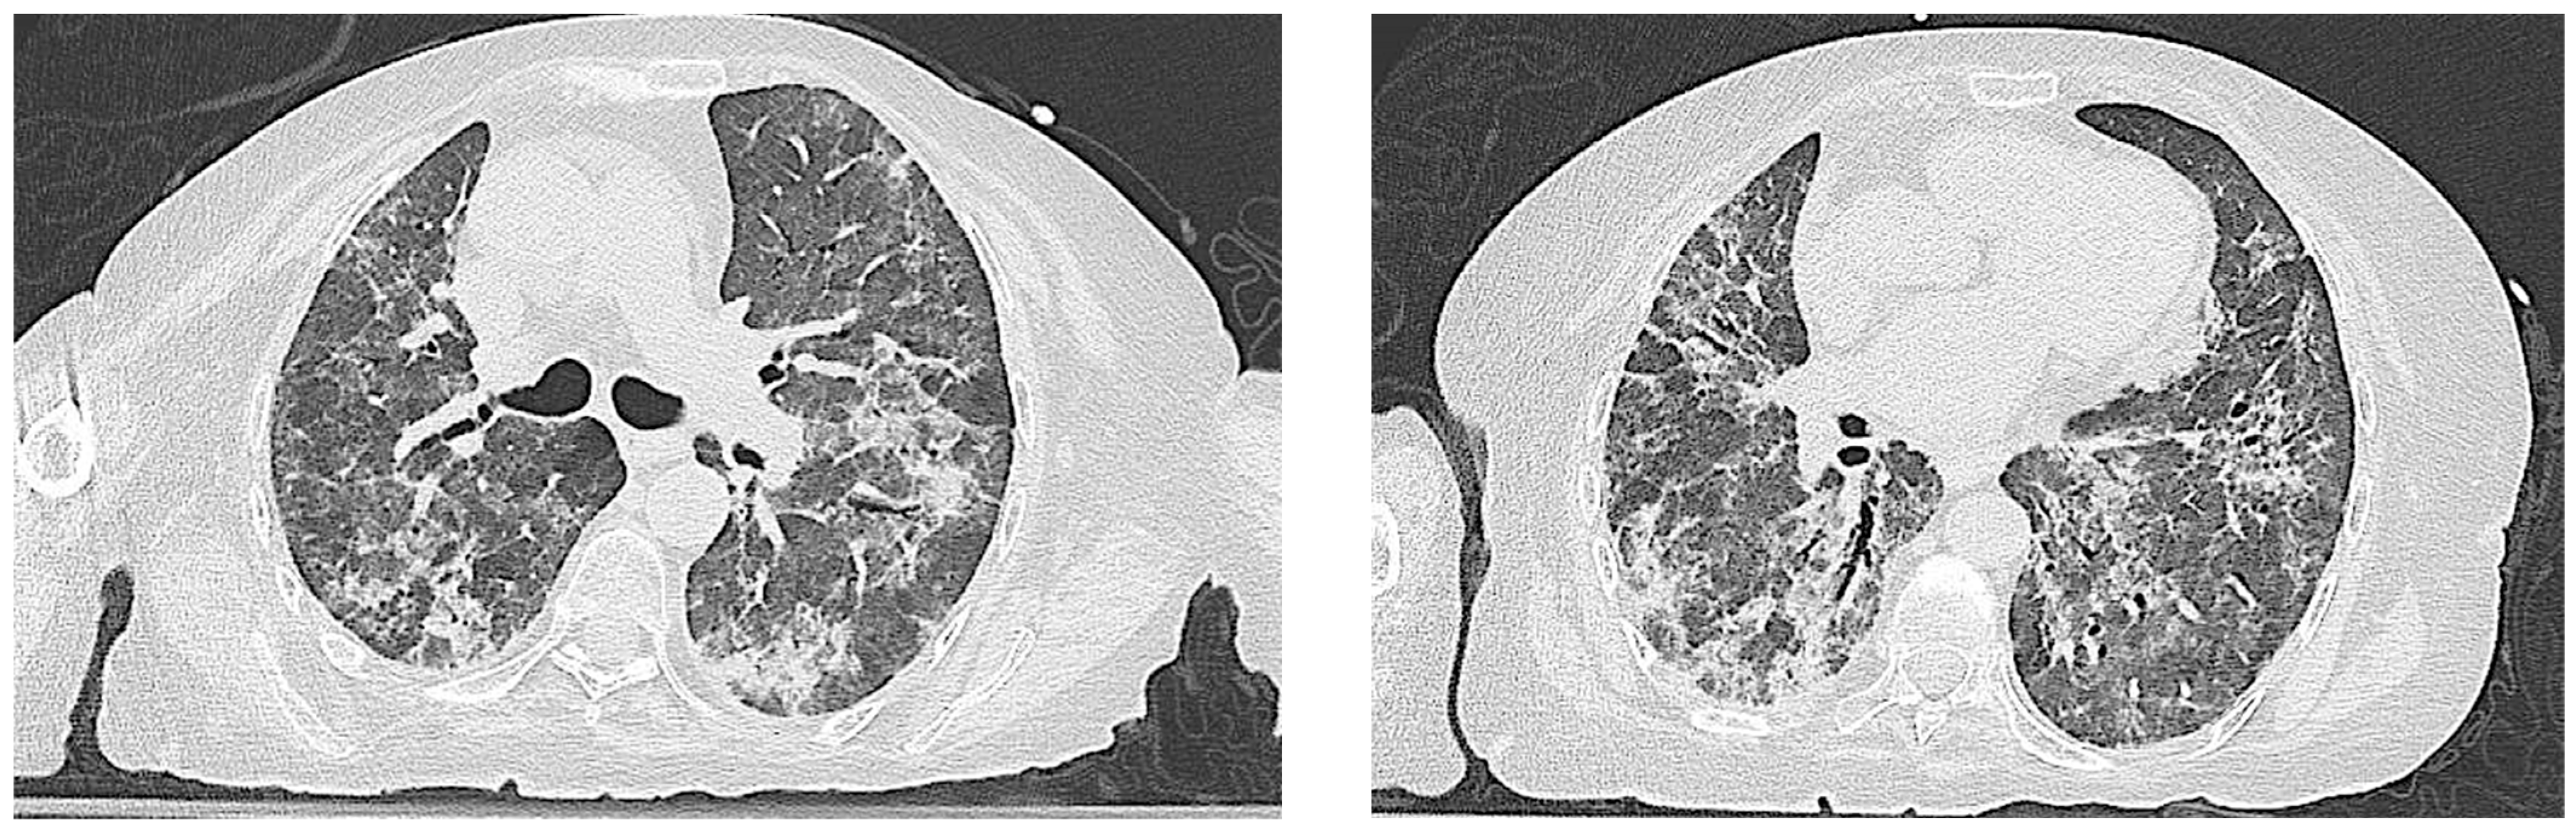

| Our patient | 68 | female | - ASyS - SD | - ANA (anti-Golgi pattern 1:1280) - anti Ro/SSA - anti PL-7 | - Raynaud Phenomenon: no - Arthralgia: no - Muscle weakness: no - Muscle enzyme elevation: no - Dyspnea: yes | NSIP | - Methylprednisolone bolus therapy (1 g/day for 3 days) - IVIG therapy (400 mg/Kg per day for 5 days) - Mycophenolate mofetil (3 g/day) - Nintedanib (300 mg/day) | The patient passed away 3 months after the initiation of immunosuppressive therapy |